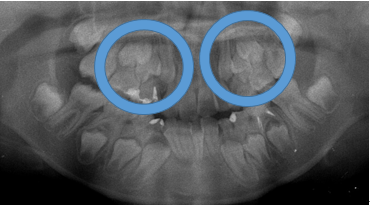

よく診る、難しい症例(奥歯の隙間)